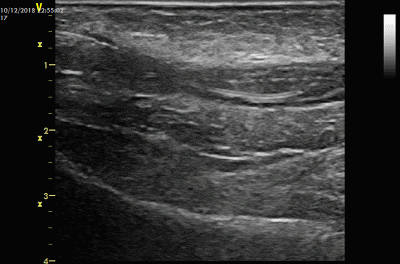

经过这样的溶栓,血栓可以发生以下一些变化

部分血栓溶解成液体

部分大块血栓裂解成小块血栓

血栓变得松软

血栓当中出现一条“通道”,这是由于导管经过时的挤压和溶栓作用产生的

部分血栓溶解成液体,部分大块血栓裂解成小块血栓